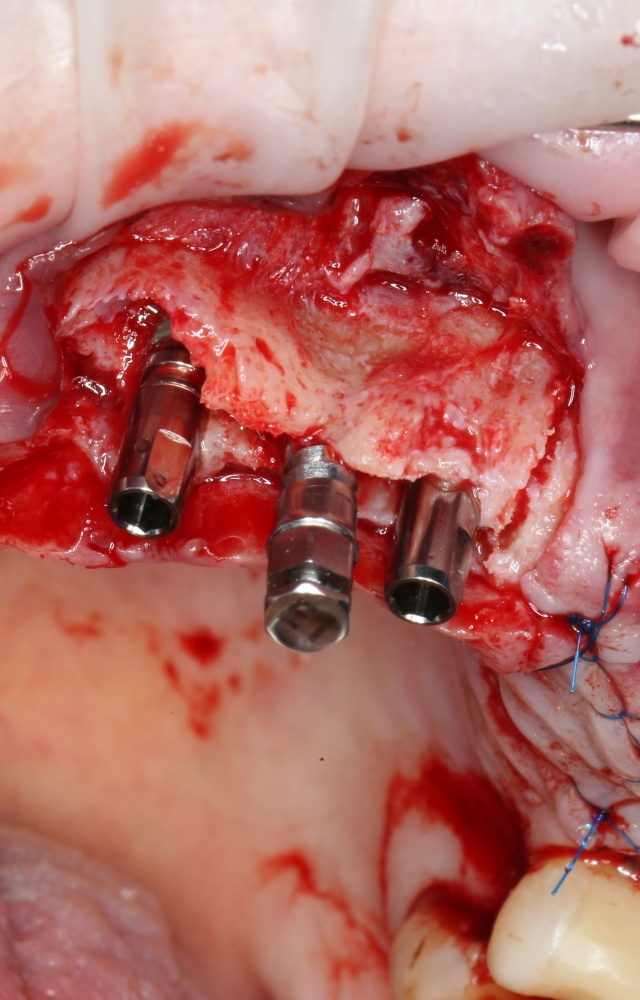

Установка имплантатов.

Напомню, что для этой работы я выбрал субкрестальные имплантаты Ankylos C/X. Они прекрасно сочетаются с любым методом остеопластики.

Я не планирую установку супраструктур или коронок, поэтому на уровень первичной стабильности можно положить болт. Даже наоборот — чем меньше крутящий момент при установке, тем лучше. Для имплантатов Ankylos и подобных им, это особенно важно. В общем, момент силы при установке — не более 10-15 Нсм.

Ремарка: имплантаты с предустановленными имплантодержателями хороши тем, что с ними легко контролировать позиционирование имплантатов. В случае с Ankylos С/Х - еще и крутящий момент. Имплантодержатель должен отсоединяться от имплантата с легким щелчком. Если его клинит, и тебе приходится прикладывать для этого усилия, то ты, однозначно, превысил момент силы во время установки имплантата. Следовательно, жди проблем.

Глянем на то, что получилось:

Осталось адаптировать костный блок (убрать острые края), проверить его фиксацию и, при необходимости, добавить винты. Десятисекундное дело.